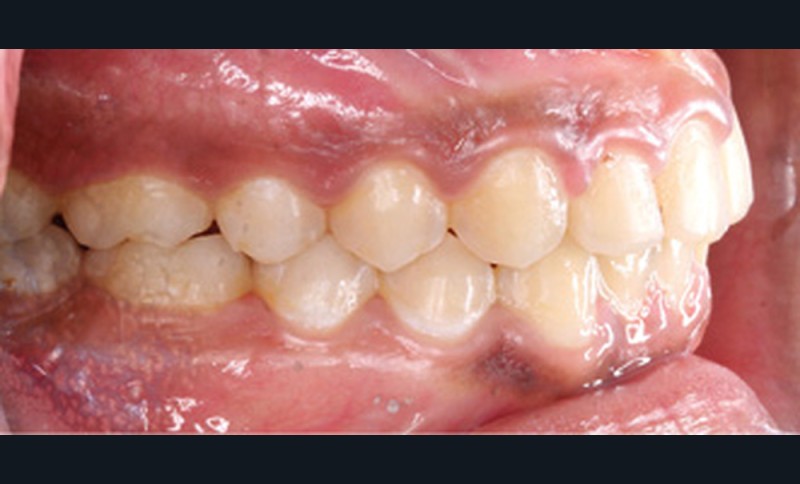

Examen clinique (fig. 1a-h)

À l’examen de face, Anisa présente un visage ovalaire, des hémifaces symétriques, des lignes horizontales parallèles, une augmentation de l’étage inférieur, une occlusion labiale légèrement forcée et des dents mandibulaires exposées au sourire. Les profils général et sous-nasal sont concaves avec un angle naso-labial augmenté et une prochéilie inférieure.

L’examen clinique endo-buccal révèle une denture adulte jeune avec un inversé d’articulé antérieur de 13 à 23, des tatouages gingivaux ethniques et des taches de décalcifications, un parodonte sain mais un brossage insuffisant.

L’arcade maxillaire est en V et la voûte palatine profonde. L’arcade mandibulaire a une forme en U (non-concordance des formes d’arcade) et présente des malpositions des dents cuspidées. La médiane mandibulaire est décalée à gauche de 2 mm ; le recouvrement antérieur est de 2 mm ; les molaires sont en classe III avec un surplomb inversé.